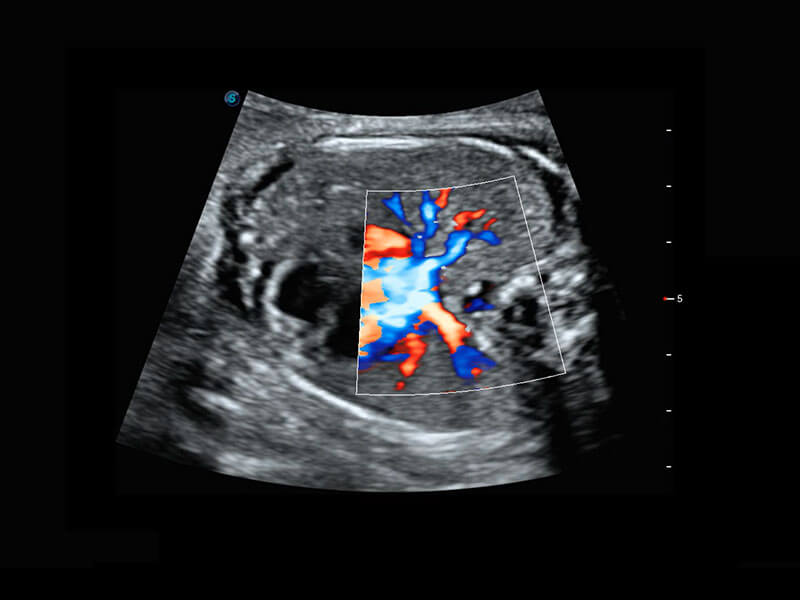

P60在胎儿早孕期超声筛查中为您带来优异的图像质量。

早孕-胎心

胎儿体循环